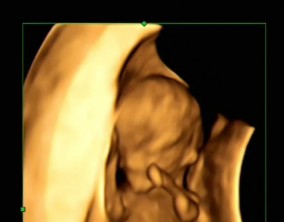

믿음 끝에 찾아온 첫 기적

의료진분들의 따뜻한 말 한마디와 친절한 행동 하나하나가 힘든 난임 치료 과정에서 큰 도움이 되었습니다. 그 진심 어린 마음이 앞으로도 많은 난임 부부들에게 변함없이 전해지…